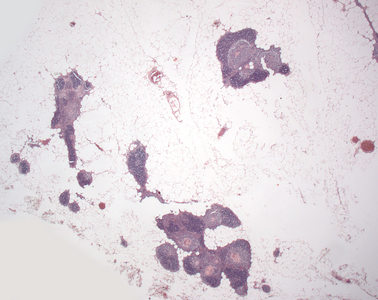

Präparat 13: Thymus (erwachsener Mensch), Gewebsschnitt, H.-E.

Hassall-Körperchen

kugelige, azidophile Gebilde aus zwiebelschalenartig zusammengelagerten Epithelzellen im Mark des Thymus. In ihrem Inneren befindet sich Detritus aus abgestorbenen Zellen.

Nach der Pubertät fällt der Thymus der Involution anheim. Dabei tritt vermehrt Fettgewebe an die Stelle des Grundgewebes (Vakatfett), das alle Merkmale des univakuolären Fettgewebes besitzt (s. auch Präparat 11). Vor allem die Rinde des Thymus wird durch dies Fettgewebe ersetzt, so dass von dem ehemaligen umkapselten, zusammenhängenden Organ (siehe vorangehendes Präparat) nur noch einzelne lymphatische „Inseln“ in einem „Meer“ von Fettgewebe erhalten bleiben.